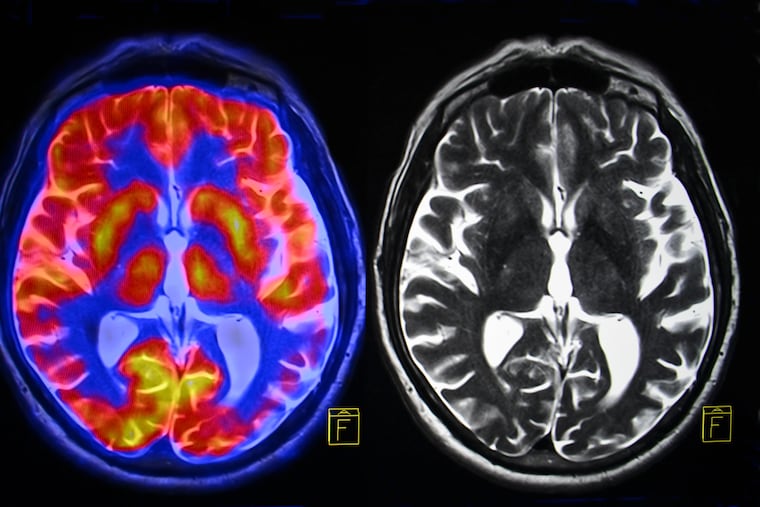

An analysis of MRIs from 13,600 people revealed a slight correlation between brain volume and scores on a test of “fluid” intelligence — a measure of logic and reasoning ability.

That suggests other factors play a much bigger role in intelligence, such as perhaps the size of certain regions of the brain or the quality of the connections between them — a hypothesis the researchers plan to examine in future studies. For example, previous research has found that the cortex, an outer layer of gray matter in the brain, tends to be thicker in women, said lead author Gideon Nave, an assistant professor of marketing at Penn’s Wharton School.

Though the researchers found a connection between brain size and intelligence, it was weak. The participants included lots of people with smaller brains but quick wits, and plenty of larger-brained folks who were not so sharp. In statistical terms, the correlation between brain volume and smarts was 0.19 (on a scale of zero to one).